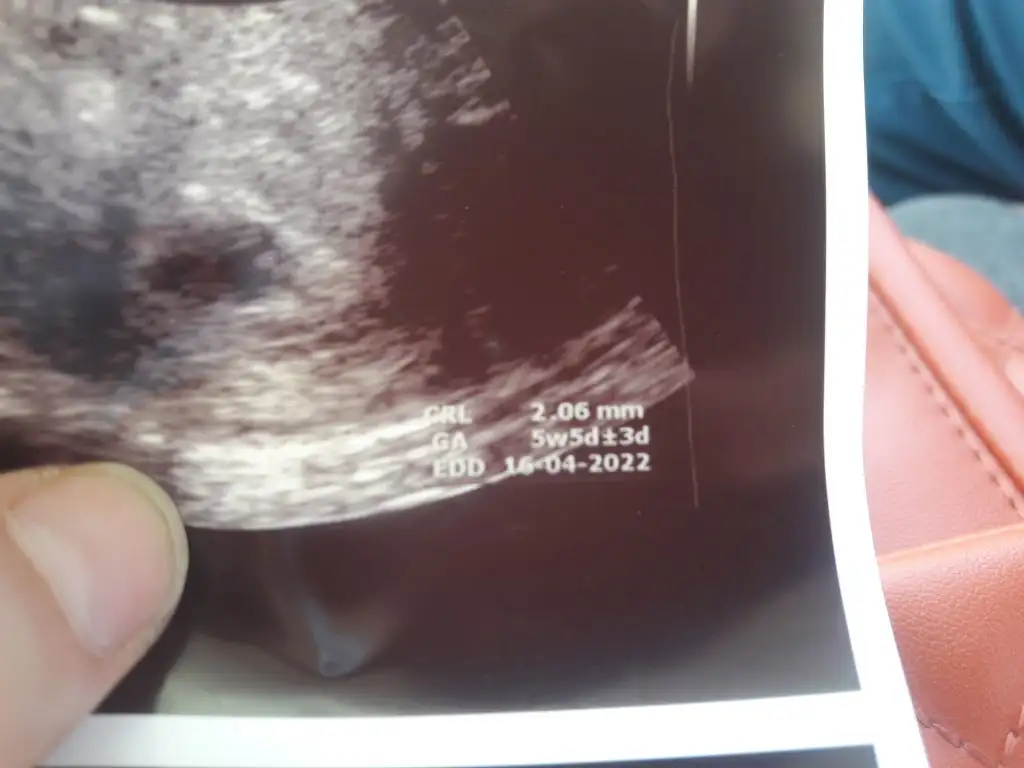

Kızlar selam bugün kontrolüm vardı ama ne doktorum nede ben anlayamadık. Doktorum sende çözemediğim biseyler var kesenin içini hala net göremiyorum gelişen bişey yok ama küçükte olsa fetüs var gibi senin en basta degerlerin düştü sonra yükseldi orda bi 10gün bi kaybımız oldu.o yüzden bu durumda.kestirip atamam küçükte olsa fetüs görünüyo.bu olumluya dönermi bilemem dedi.10gun öncekiyle bugunki ultrason kağıdımı atıyorum bişey söyleyin valla kafam çorba oldu remziye_06 remziye_06

Eklentiler

• 20210809_201234.webp

20210809_201234.webp

22,9 KB · Görüntüleme: 80

• 20210819_115042.webp

20210819_115042.webp

20,6 KB · Görüntüleme: 75